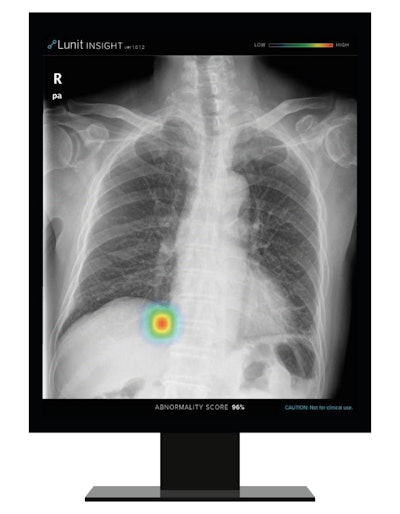

South Korea-based Lunit noted that its Insight CXR AI software is helpful for real-time detection of 10 common findings on chest x-rays and enables triage of cases to focus on those with likely abnormalities. The company said that the software's accuracy rate is high, ranging from 97% to 99%.